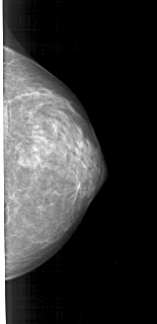

A_1379_1.LEFT_MLO

LEFT_MLO LINES 5041 PIXELS_PER_LINE 2596 BITS_PER_PIXEL 12 RESOLUTION 43.5 OVERLAY